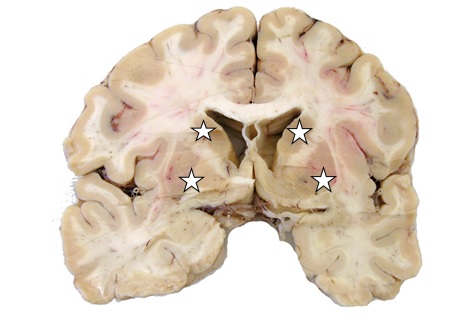

W skład jąder podkorowych mózgu/zwojów podstawy (basal ganglia) wchodzi ciało prążkowane (corpus striatum), które składa się z czterech wymienionych podjednostek (oznaczonych gwiazdkami). W skład ciała prążkowanego nie wchodzi: